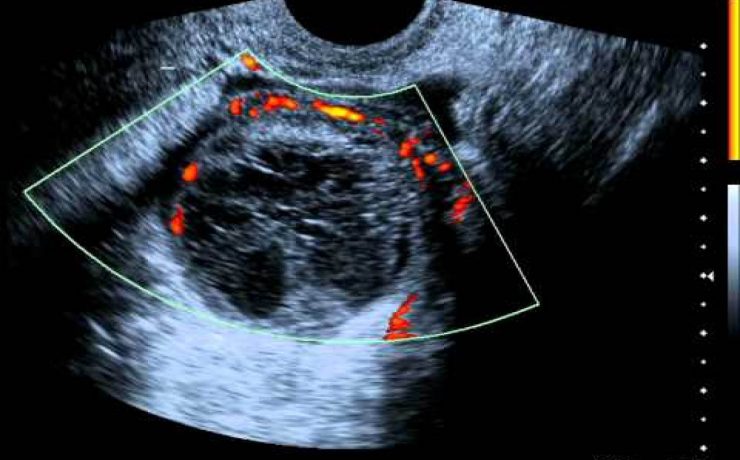

Correlación ultrasonográfica e histopatológica de los tumores de ovario

El cáncer de ovario, constituye el 2 % de las afecciones malignas de la mujer con una alta mortalidad, aproximadamente las dos terceras partes se presentan con lesiones muy avanzadas en el momento del examen imagenológico,1-4 trae por consecuencia una supervivencia menor de la paciente y un aumento del costo